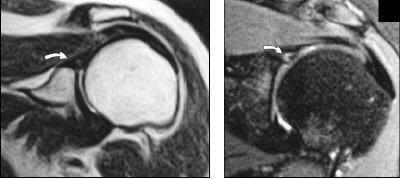

| Thirty-eight-year-old women with shoulder pain. Left, T2-weighted coronal 0.2-tesla image (TR/TE, 3,350/94.5) shows suspected abnormality in superior labrum (arrow). STIR coronal imaging was attempted, but patient could not remain motionless long enough. Right, T2-weighted coronal 1.5-tesla image (2,500/68) shows definite superior labral anteroposterior tear (arrow) that was confirmed at arthroscopy. Magee, T, Shapiro, M, Williams D, "Comparison of High-Field-Strength Versus Low-Field-Strength MRI of the Shoulder," (AJR 2003, Vol.181, pp.1211-1215). |

Magee and co-authors concluded that 1.5-tesla MR imaging was inherently superior to low-field MRI, offering better signal-to-noise ratio (SNR), faster imaging, and thinner slices.

"This most likely resulted in better visualization of subtle signal abnormalities...these small tears did not resolve as well on the low-field-strength units because the larger slice thickness needed to maintain adequate SNR required more volume averaging," they wrote.